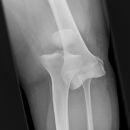

Kniegelenk